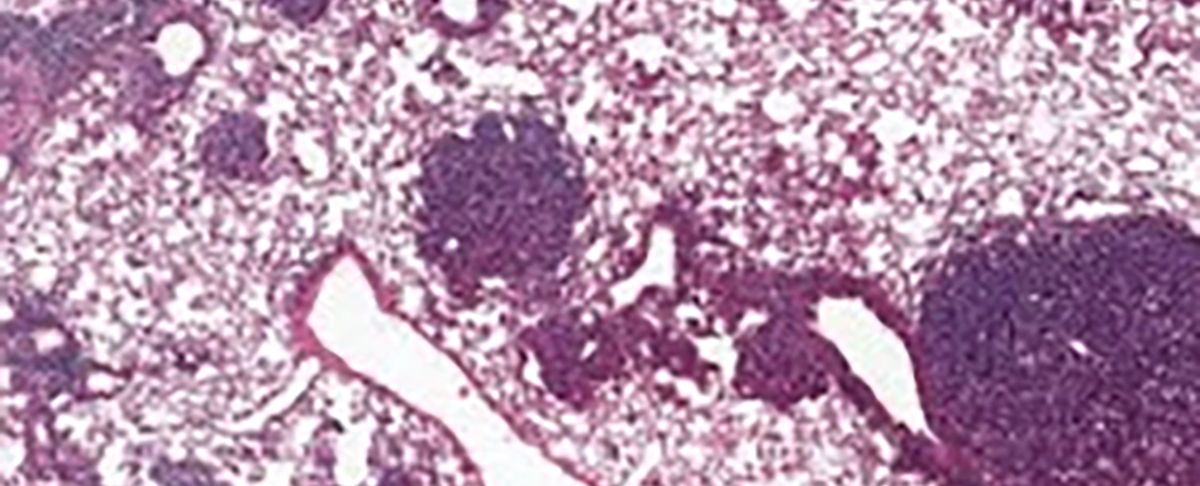

Mediante análisis exhaustivos en células pulmonares, los científicos detectaron niveles elevados de una proteína llamada NUPR1 en los especímenes más antiguos, lo que modificaba el procesamiento del hierro en el organismo. Los resultados de esta investigación fueron publicados en la prestigiosa revista Nature.

Trabajando con células madre alveolares tipo 2, fundamentales para la regeneración pulmonar, los investigadores notaron que los niveles aumentados de NUPR1 restringen tanto el crecimiento saludable como el desarrollo tumoral.